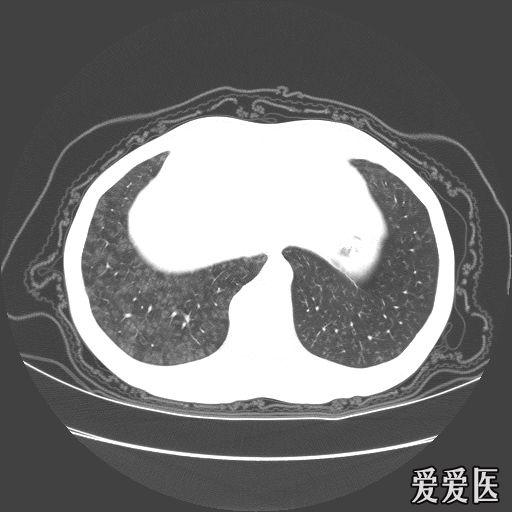

经典肺部病变ct - 医学影像学讨论版 - 爱爱医医学论坛-爱爱医医学网

肺气肿的影像诊断